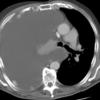

huge effusion CT